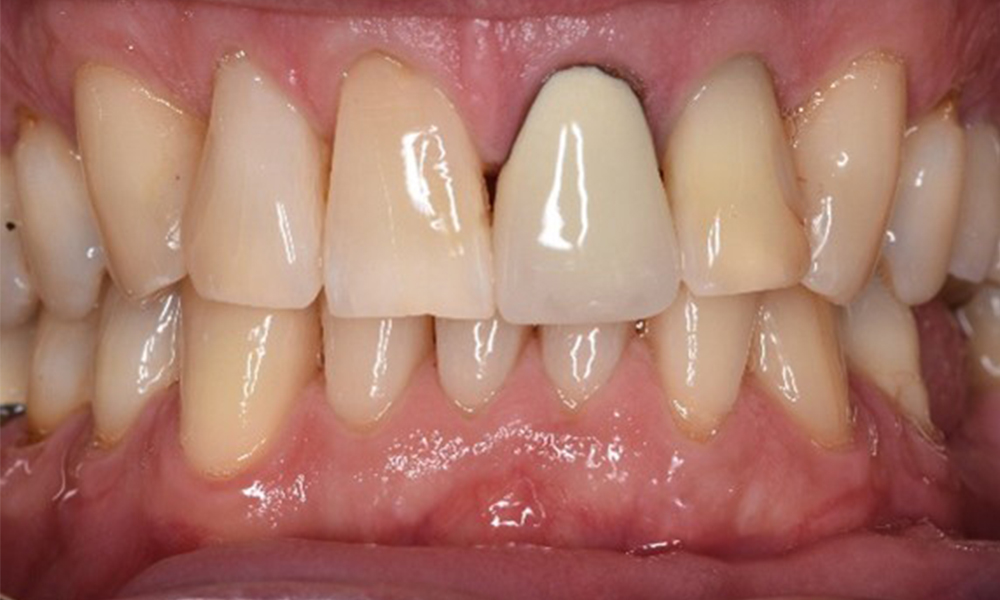

The healthy patient with early periodontal disease

The 68-year-old patient has no general health conditions and is not taking any medication that may be relevant to her oral health, and her lifestyle does not pose any particular risk. The patient has two dental implants (3rd quadrant, for five years) and a previous case of periodontal disease (stage IV, grade B periodontitis) with tooth loss. Currently the periodontal conditions are stable. However, periodontitis significantly increases the biological complications of implantations and there is a risk of implant loss (21). Four recommendations can be determined for the prophylaxis session. more